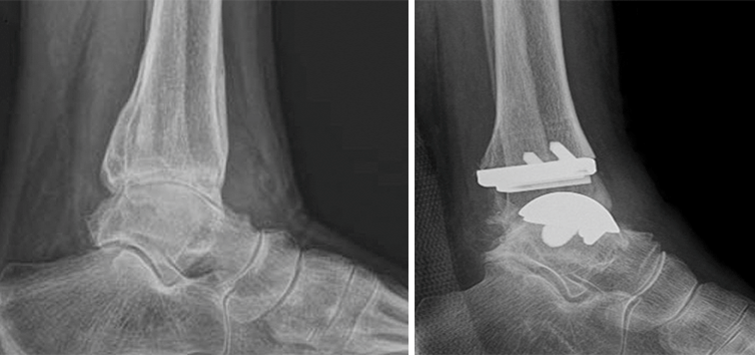

(五)踝关节炎

踝关节炎是踝关节软骨退化引发的炎症性疾病,主要表现为疼痛、肿胀、活动受限,常见于中老年或关节损伤人群。本中心采用关节镜下滑理术,截骨矫形术,关节融合术和踝关节置换术治疗不同类型的踝关节炎。

图15:全踝关节置换术。